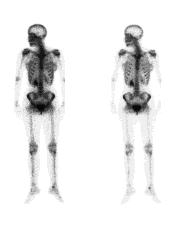

Osteoporosis is a disease that thins and weakens the bones. Your bones become fragile and break easily, especially the bones in the hip, spine, and wrist. In the United States, millions of people either already have osteoporosis or are at high risk due to low bone mass.

Osteoporosis is a silent disease. You might not know you have it until you break a bone. A bone mineral density test is the best way to check your bone health.